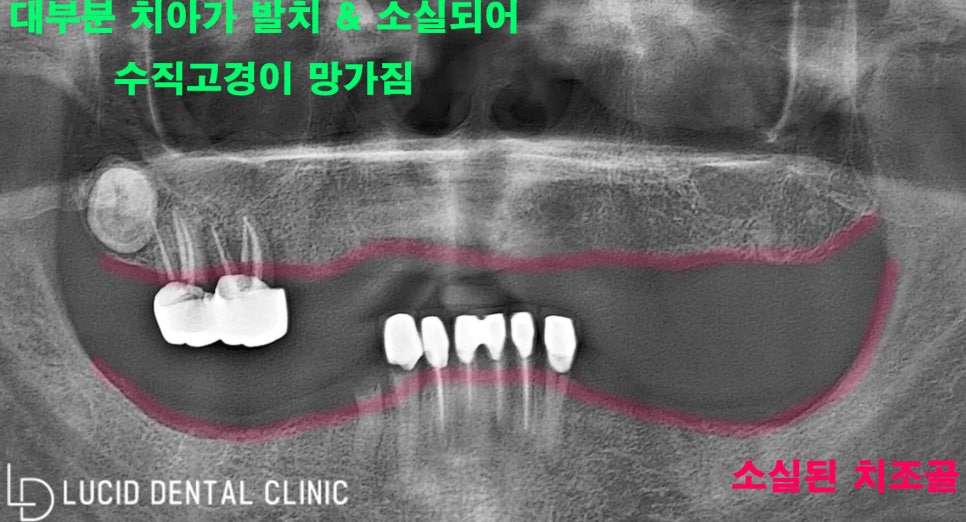

대부분 발치가 된 걸로 보이고,

치은퇴축도 심하게 일어났네요.

게다가 위아래 둘 다 치아가 많이 없어서

'수직고경'도 많이 무너져 있었습니다.